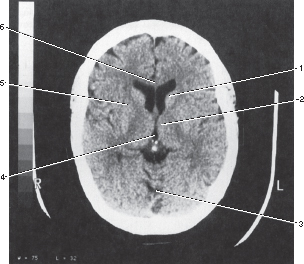

10

4

3rd ventricle

11

3

Vermis of cerebellum

Which of the following areas of the head commonly becomes calcified?

2 and 3